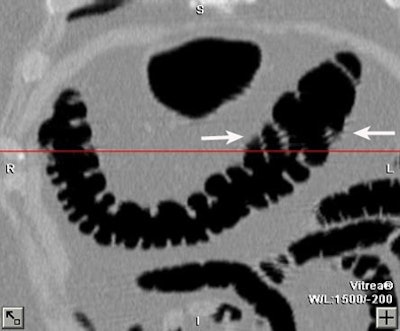

| A colonoscopically and pathologically proven 6- to 9-mm polyp in the transverse colon cannot be seen, even in retrospect, due to technical error. Above, representative axial image shows excellent preparation and distension of the transverse colon. On both the prospective and retrospective interpretation, no lesion could be identified in the transverse colon. Below, coronal reformation of the transverse colon shows good distension and good preparation. There is some motion artifact (arrows) from breathing which minimally obscures a portion of the transverse colon. |

There were 15 technical errors, and in seven of the 15 the lesion could not be identified retrospectively despite excellent bowel prep and good distension. Of these, he said, four were flat lesions, and three were located on a fold. Other technically challenging cases were complicated by the presence of stool or fluid in the involved segment, or by failure to achieve good distension in the involved segment. A breathing artifact prevented visualization of an 8-mm polyp in one patient.